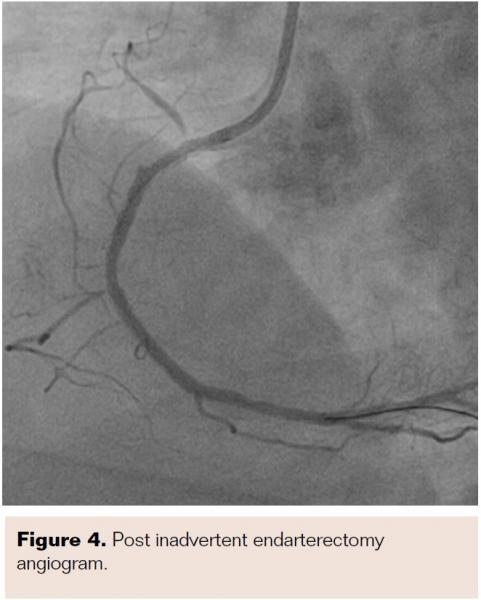

He was admitted and was managed for acute coronary syndrome – unstable angina. He was managed as per guideline-directed medical treatment and was later taken for coronary angiogram after written informed consent. A precatheterization profile was performed and a radial approach with a 5 Fr Tiger catheter (Terumo) was chosen. The left coronary system showed no significant lesions, but Mehran type III in-stent restenosis (ISR) was noted in the ostioproximal RCA stent (Figure 1). Accordingly, the decision was made to proceed with repeat PCI, and when the 6 Fr Judkins right 3.5 guide catheter (Medtronic) was exchanged and manipulated, the patient reported severe chest pain. Echocardiogram showed ST elevation in inferior leads. The check angiogram showed ostial right coronary total occlusion (Figure 2A), so the RCA was quickly wired with a 0.014" balance middle weight floppy wire (Abbott Vascular) and the ostioproximal lesion was predilated with a 2 mm x 10 mm Sprinter Legend semicompliant balloon (Medtronic) (Figure 2B). Postdilatation cine showed a longitudinal homogenous opacity moving from the proximal RCA and embedded into the distal RCA, causing TIMI 0 flow (Figures 2C and 2D). Because the first differential for TIMI 0 flow was thrombotic occlusion, our strategy was to disintegrate the thrombus via balloon manipulation. After failure on multiple attempts, thrombosuction with a 6 Fr, 140 cm Thrombuster II (Kaneka Medix Corp.) was performed and a pale soft tissue was retrieved (Figure 3A). Imaging post thrombosuction showed clearing of the ISR and TIMI III flow across the RCA (Figure 4). Histopathology of the retrieved tissue reported endothelial cells with intermittent muscle cells (Figure 3B). The ostioproximal RCA was stented with a 3 mm x 18 mm Xience Pro everolimus-eluting coronary stent (Abbott Vascular) and TIMI III flow was noted with resolution of chest pain and ECG changes (Figure 5). The patient was closely monitored for 48 hours and was discharged.

Other factors that contribute to ostial coronary dissections are guidewire manipulation, inadvertent balloon dilatation, or stent placement in false lumen. In our case, careful assessment of cine images post procedure revealed that the guidewire probably created a false track, which was later dilated with the balloon. Hence, the longitudinal homogenous opacity which was seen in post dilatation cine was actually the neoendothelium stripped off inadvertently.